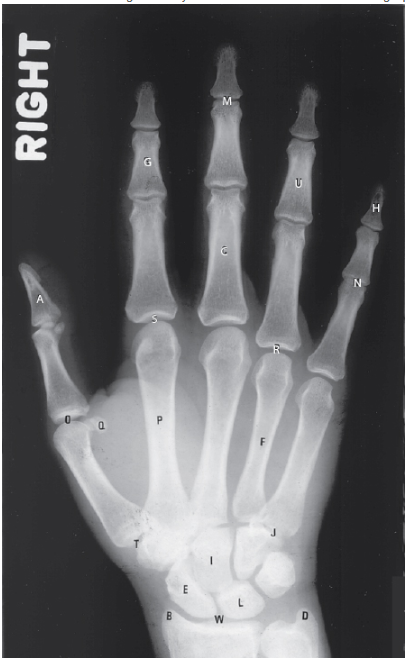

L Identifies:

B - Lunate

The eight carpal bones are well visualized in this PA projection of the hand and wrist. The letters E (scaphoid) and L (lunate) are in the proximal carpal row. The capitate (I) is seen in the distal carpal row; just lateral to the capitate is the carpal trapezium, seen articulating with the base of the first metacarpal. The PA projection of the hand provides an oblique projection of the first finger (thumb).